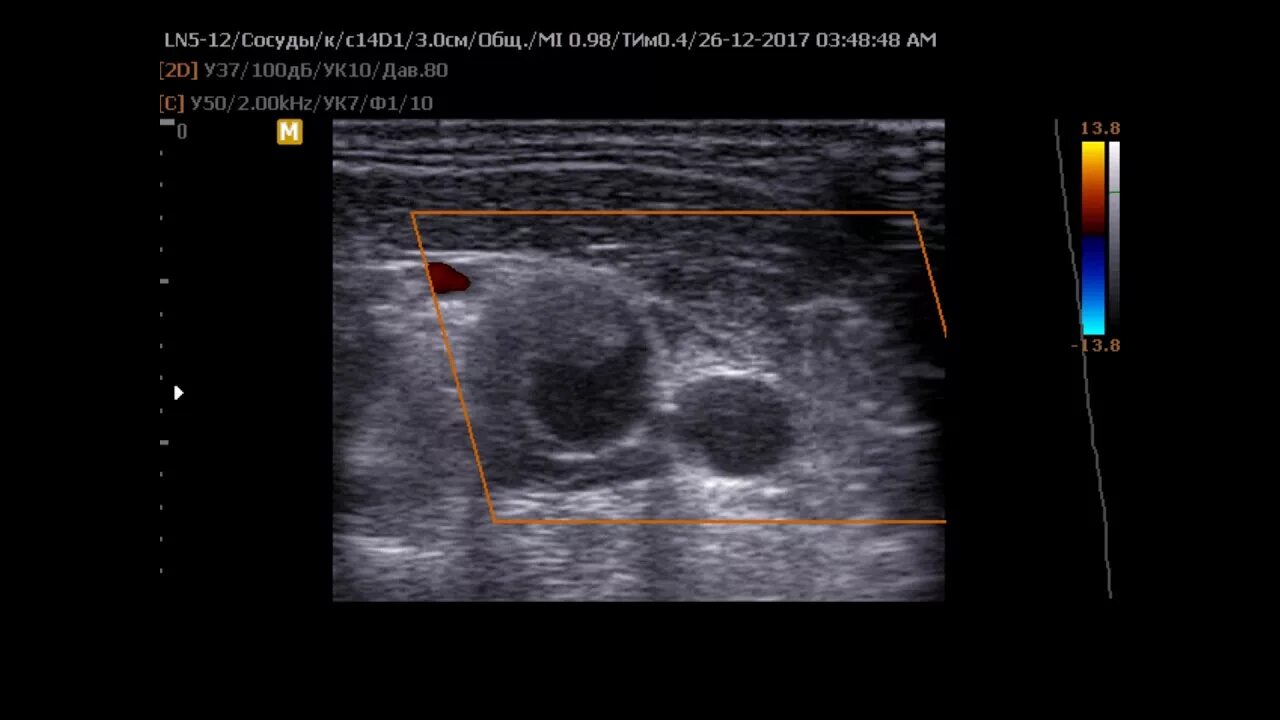

Узи шип